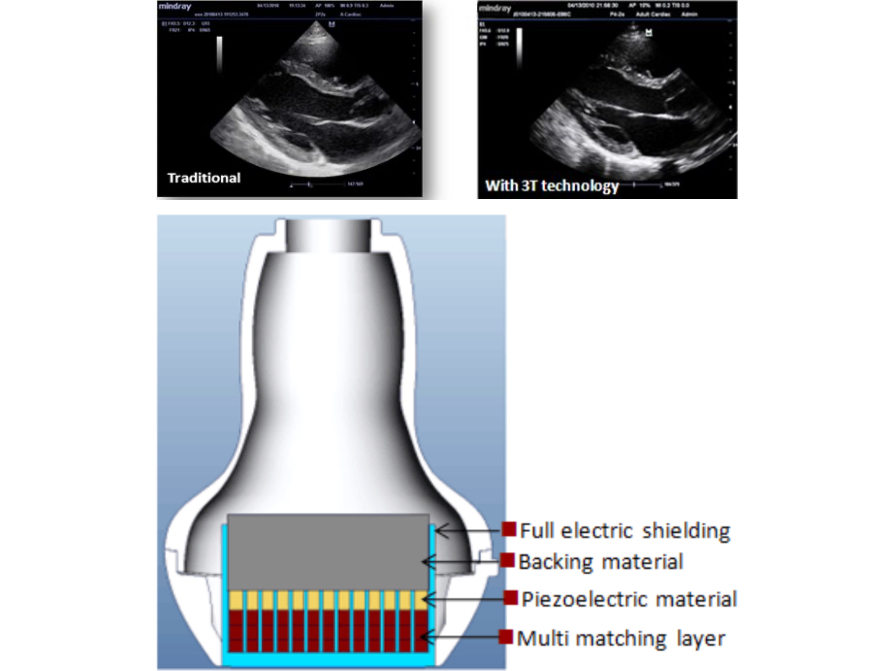

MindrayŌĆÖs patent transducer technology to increase image bandwidth and transmission efficiency.

- Triple-matching layer design for higher sensitivity, wider bandwidth, and improved S/N

- Total-cut design for lower cross-talk noise, better directivity, and improved lateral resolution

- Thermal-control design for better acoustic transmission